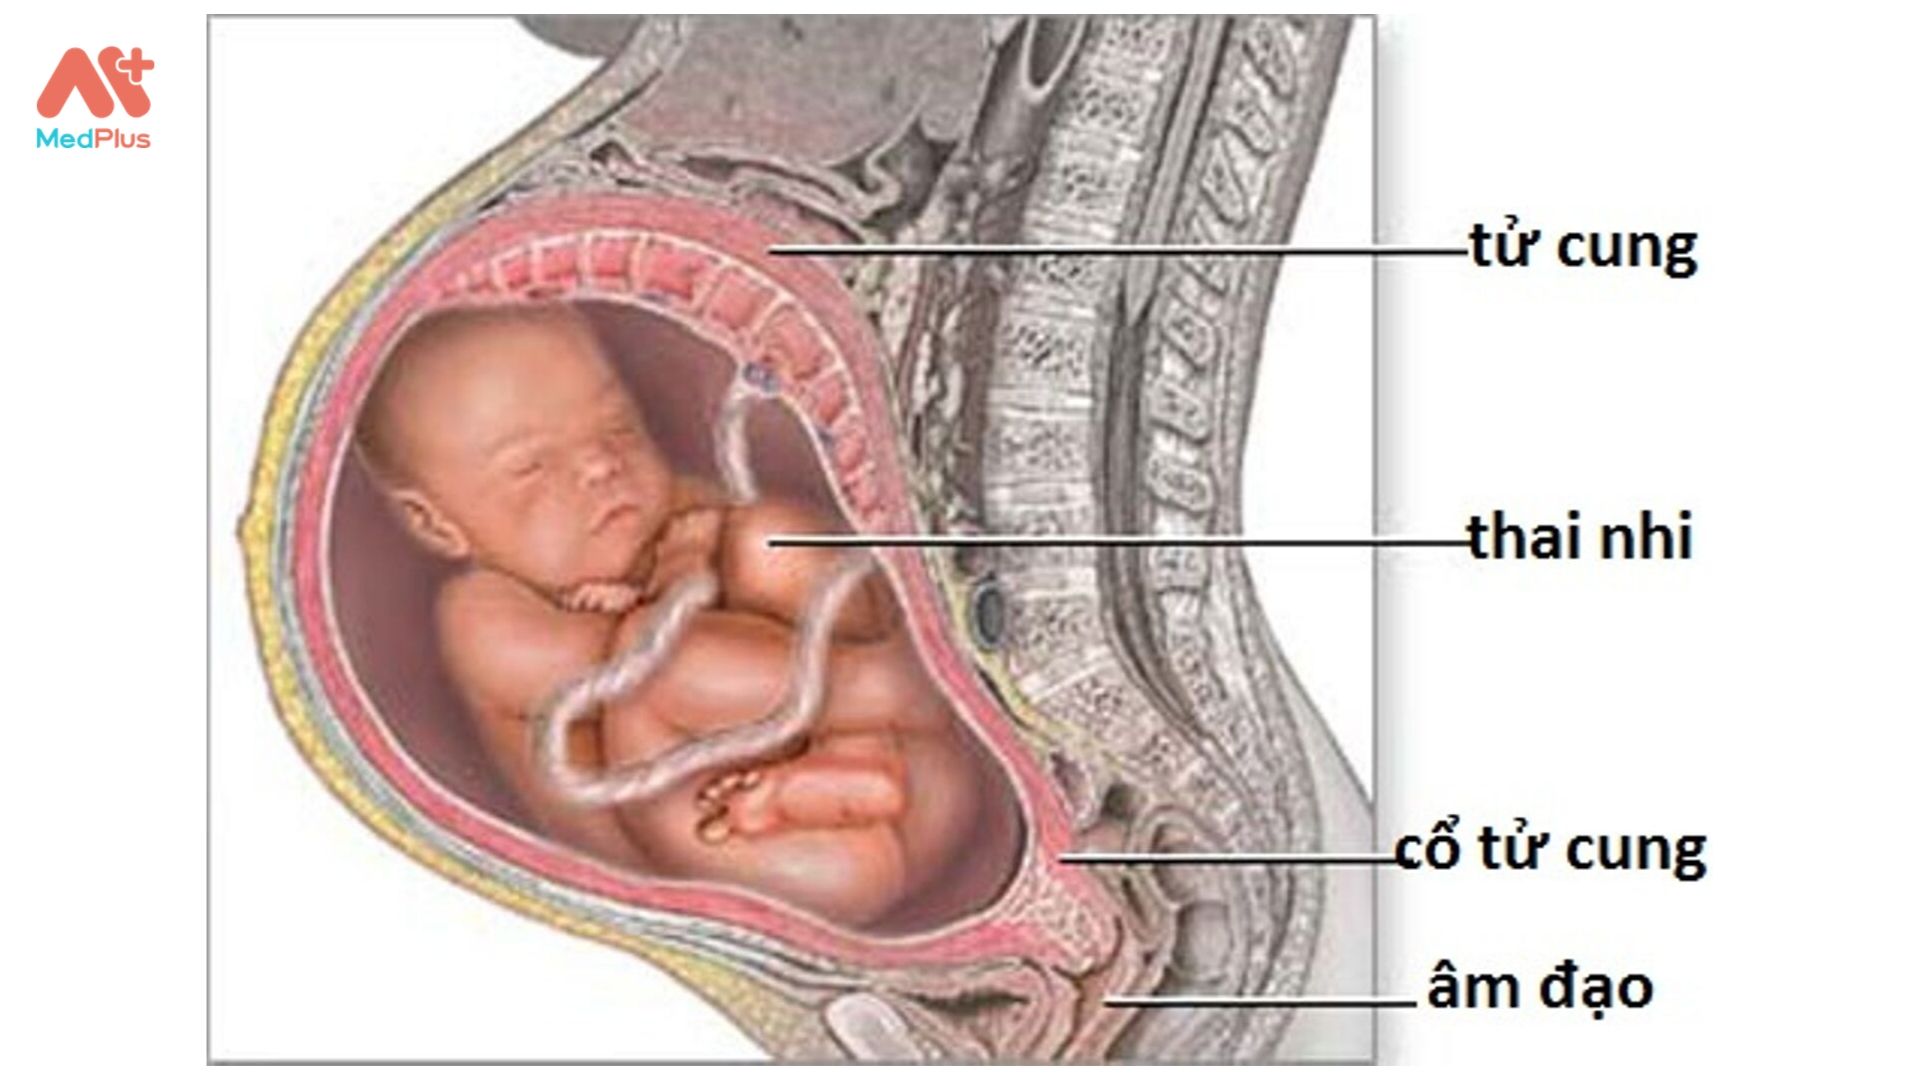

Во время беременности, положение плода имеет большое значение для мамы и малыша. Одним из типичных положений является продольное предлежание головное. В этом положении голова малыша находится внизу, а ножки - наверху. Это положение достаточно распространено и предпочтительно для естественных родов.

Расположениребенка в матке

Расположение ребенка в матке